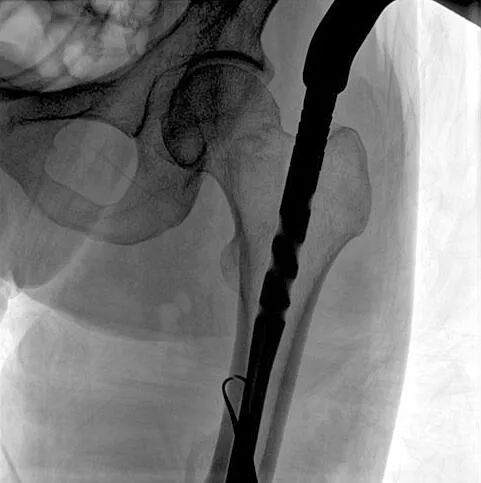

患者:男性,43歲,左股骨干骨折髓內(nèi)釘內(nèi)固定術(shù)

醫(yī)院:南京應(yīng)天骨科醫(yī)院

術(shù)中使用普愛醫(yī)療大平板一體式C形臂進行透視,判斷骨折情況及克氏針、髓內(nèi)釘?shù)冉饘僦踩胛锏奈恢茫M行調(diào)整。C形臂準確的術(shù)中定位,大大縮短了手術(shù)的時間,減輕了患者的痛苦,輔助手術(shù)順利完成。

在進行髓內(nèi)釘內(nèi)固定術(shù)時,醫(yī)生需要同時觀察到入釘點和骨折部位的情況,普愛醫(yī)療大平板一體式C形臂采用30CM×30CM的平板探測器,能夠呈現(xiàn)更廣闊的成像面積,滿足大部分長骨髓內(nèi)釘內(nèi)固定術(shù)的攝片需求。

術(shù)中定位準確、出血量少,術(shù)后影像顯示股骨移位糾正,恢復良好力線,手術(shù)效果良好。